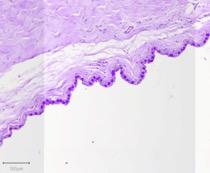

Immediately after sacrifice, the cornea was extracted from each eye to be used for histological assessments. The tissue was fixed in 10% Neutral Buffered Formalin (distributed by Epredia), embedded in paraffin, and sectioned appropriately before staining. Periodic acid Schiff was a key stain in this study that was used to detect the goblet cells in the conjunctiva.

Figure 3. PAS stain of goblet cells in naïve conjunctiva (a), surgical model (b), and chemical model (c).